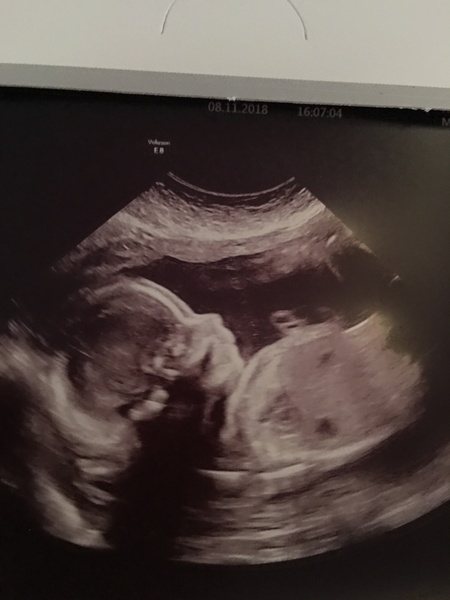

Liliana16 · 30/11/2018 22:26

This is my 20 week scan but I didn’t find out the sex. Would love to know what people think though please.

Skull theory

Shadow1234 · 30/11/2018 23:24

OP - I am going with girl for your scan xxx